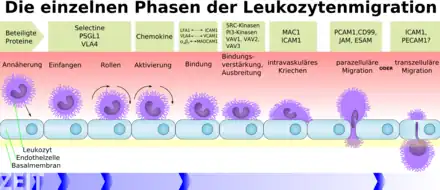

Diapédèse leucocytaire

Les molécules d’adhésion (CAM, intégrines, sélectines) libérées par les cellules endothéliales sont un signal pour les leucocytes présents dans les vaisseaux sanguins, qui dans la région inflammatoire ont tendance à quitter le milieu du courant pour s’accoler à la paroi de l’endothélium du vaisseau, par « margination », favorisée par le ralentissement du flux sanguin.

La diapédèse leucocytaire est le phénomène permettant le passage des leucocytes de la circulation sanguine jusqu'au foyer de l'inflammation. La traversée de l'endothélium par les leucocytes ou diapédèse intervient dans un segment particulier du système circulatoire : les veinules post-capillaires. On peut distinguer différentes étapes :

- Margination leucocytaire ;

- Rolling : interaction des leucocytes et des cellules endothéliales par l'intermédiaire de sélectines, adhérence faible entre une sélectine E capillaire et un carbohydrate de la cellule immunitaire ;

- Activation (activation) par interaction entre une chimiokine capillaire et une intégrine cellulaire ;

- Adhérence ferme (adhesion) entre l'intégrine cellulaire (LFA-1) et son ligand vasculaire (ICAM-1). La cellule est fixée sur l'endothélium ;

- Diapédèse : passage de la paroi endothéliale par les leucocytes, qui commence par l'adhésion cellulaire par l'intermédiaire des intégrines et de molécules d'adhésion (ICAM, en anglais : intercellular adhesion molecule).

Après la migration des leucocytes hors des vaisseaux sanguins (extravasation), les cellules inflammatoires, dont les leucocytes, se dirigent ensuite de façon unidirectionnelle par chimiotaxie, le long d'un gradient créé par les cellules locales, pour atteindre le site de la lésion.